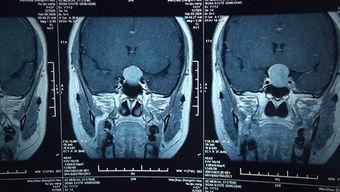

在手术前,患者需要接受一系列的检查,以确保手术的顺利进行。这些检查包括但不限于:血液检查、影像学检查(如MRI、CT等)、内分泌功能检查等。通过这些检查,医生可以了解肿瘤的大小、位置、性质以及患者的身体状况。